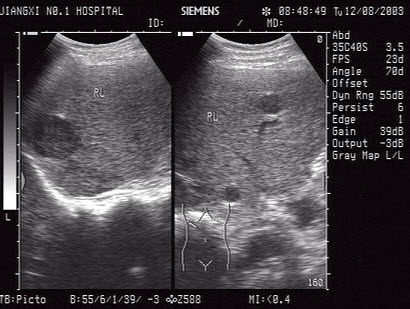

男,30岁。超声声像图如图,诊断为()